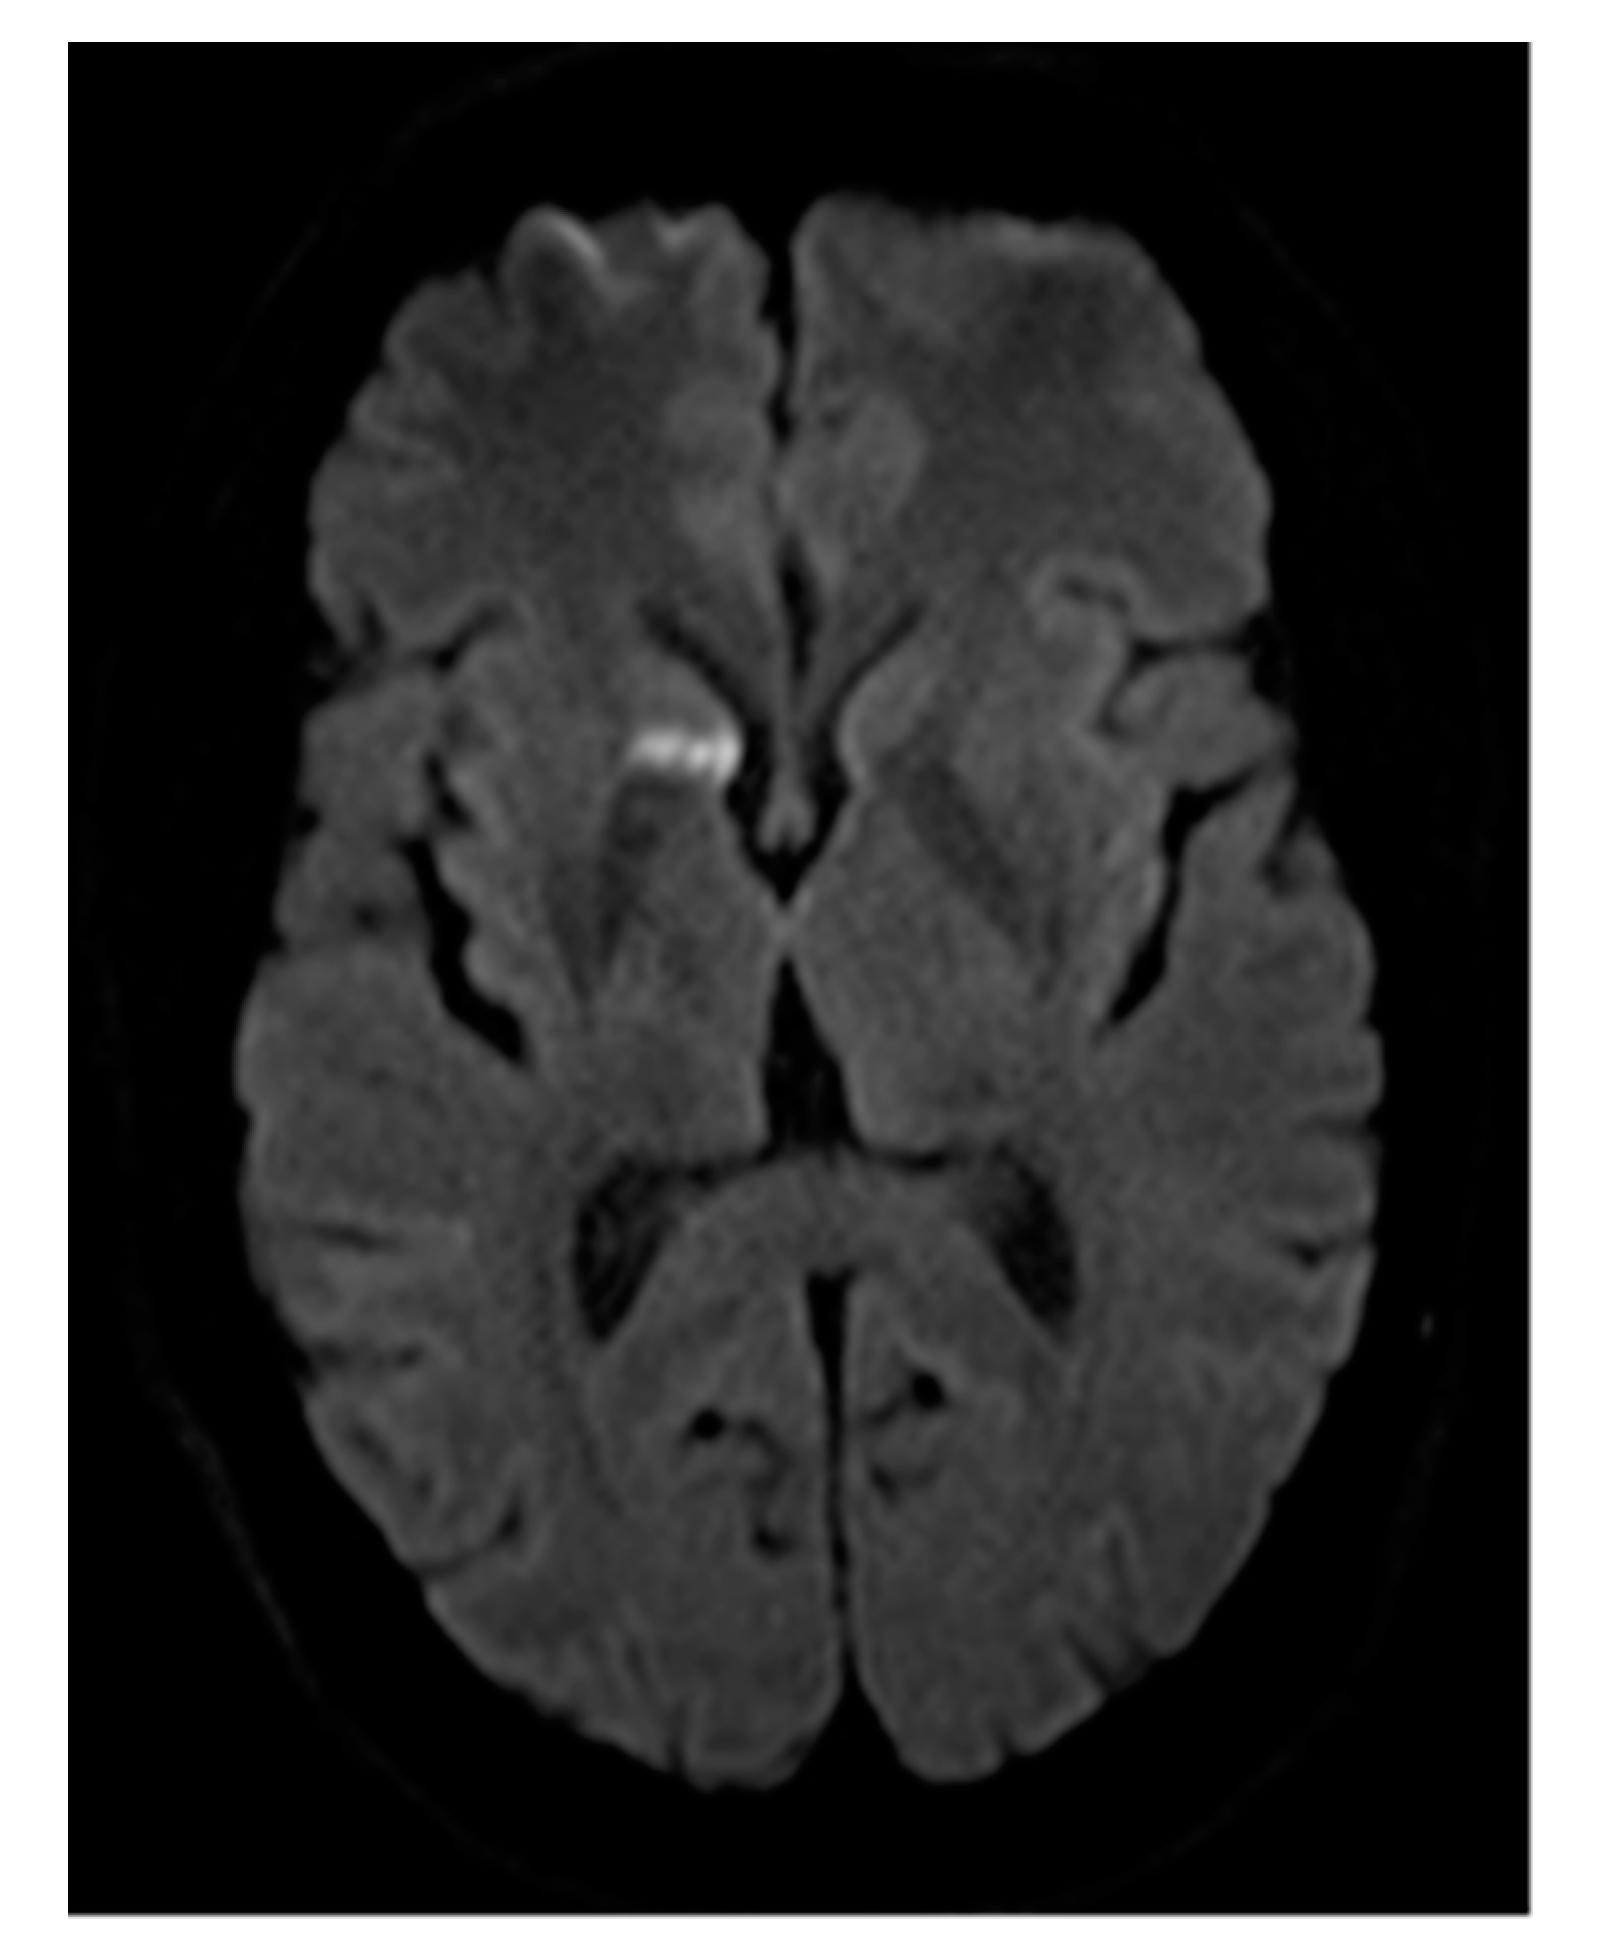

Figure 4. (ad) A giant re-perfused PAVM in the lower right lobe. In this case, pre-interventional DSA (a) shows two large feeding vessels originating from a common trunk, resulting in embolization being performed at the level of the bifurcation. With DSA performed just after implantation, (b) shows the amplatzer plug II still connected to the wire. Optimal positioning is depicted. The dynamic series in (c) shows the vascular plug (arrow) still penetrable to contrast medium, however, flow is already reduced. At 5 min post-implantation of the vascular plug (d), the feeding artery of the re-perfused PAVM is completely occluded.